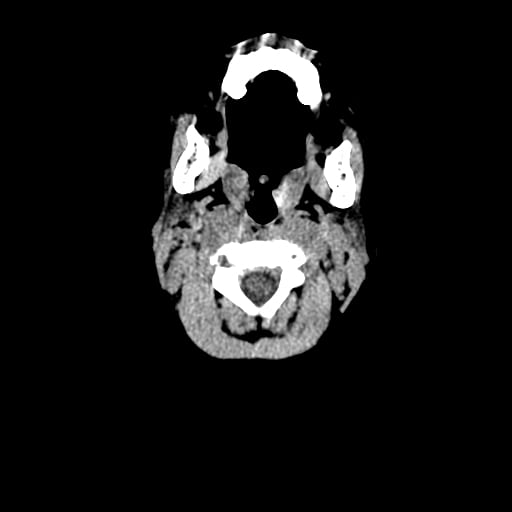

Age: 1

Sex: Male

Indication: Fall